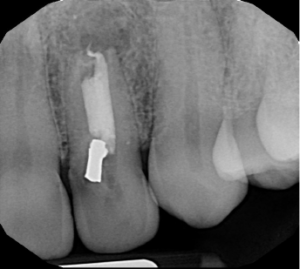

To address these complex issues, we employed a series of cutting-edge techniques for his re-treatment root canal:

- Removal of old materials: We carefully removed the previous filling and root canal material.

- LASER irrigation: This advanced cleaning method helps eliminate bacteria and debris from the root canal system.

- Calcium hydroxide medication: We applied this antimicrobial agent to further disinfect the tooth.

- Biodentine obturation: After three weeks, we filled the lower portion of the root with Biodentine, a bioactive cement that promotes healing.

- Fiber post placement: To reinforce the tooth structure, we bonded a fiber post in place